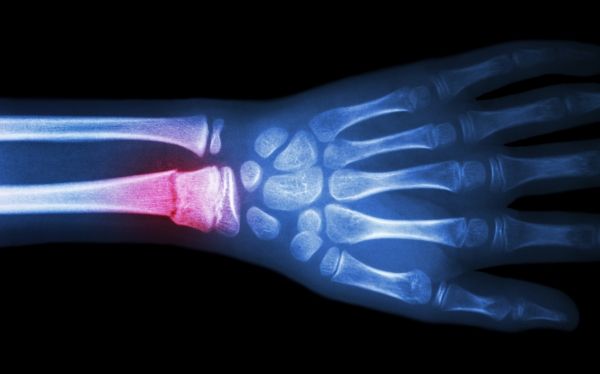

Image: In a mouse model of diabetes, a plant-grown compound helped bone fractures heal faster.  CREDIT: University Of Pennsylvania